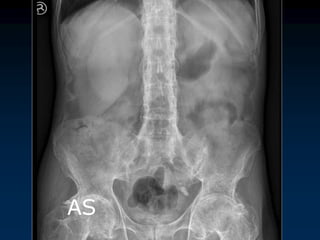

AS

Sacroiliitis

 30 year old man with LBP HLAB27+

Synovitis, subchondral edema, iliac side more common